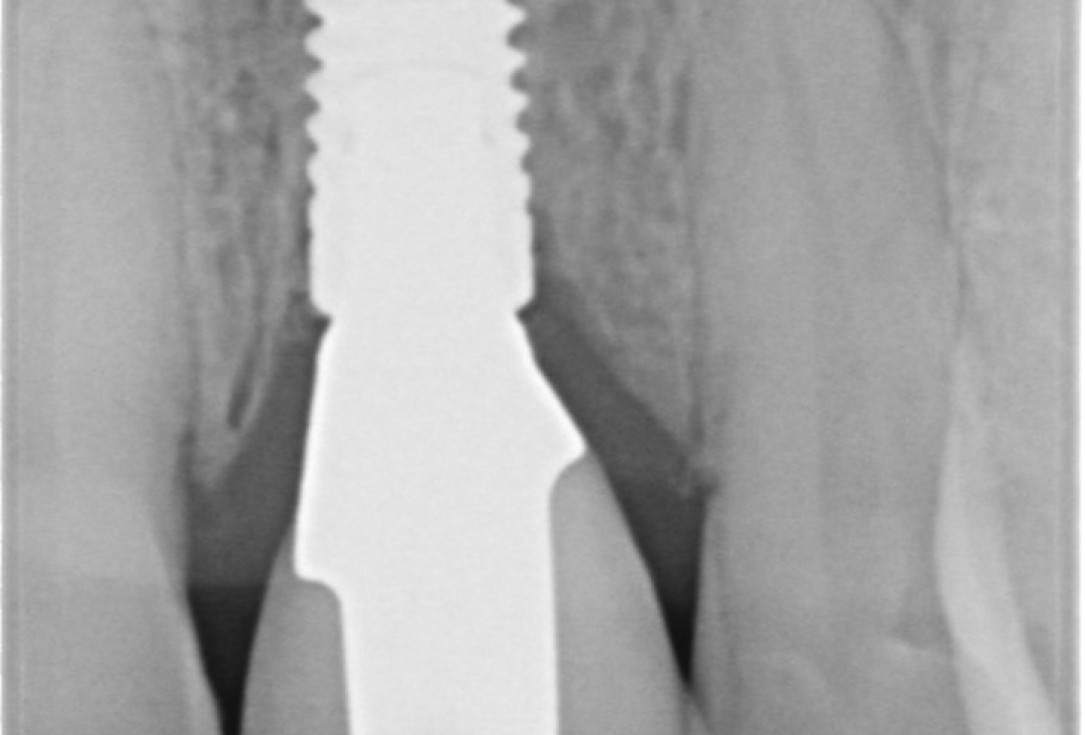

Immediate implant placement with cerabone® and mucoderm® - Dr. F. Rossi - X-ray of tooth 11Immediate implant placement with cerabone® and mucoderm® - Dr. F. Rossi

Immediate implant placement with cerabone® and mucoderm® - Dr. F. Rossi - Control x-rayImmediate implant placement with cerabone® and mucoderm® - Dr. F. Rossi

Immediate implant placement with cerabone® and mucoderm® - Dr. F. Rossi - Final x-ray controlImmediate implant placement with cerabone® and mucoderm® - Dr. F. Rossi